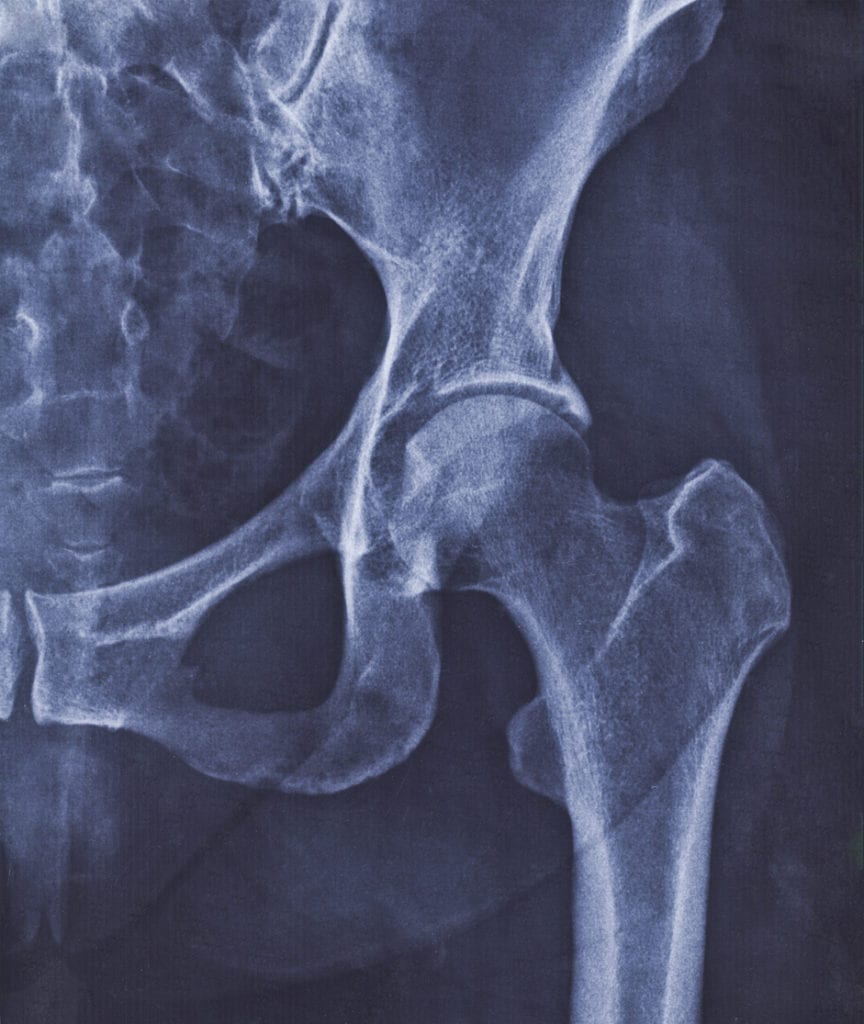

Hip replacement surgery is usually recommended for patients with severe arthritis or hip damage that renders them unable to perform daily activities and live a fulfilling life. This type of surgery involves removal and replacement of damaged parts of the hip joint that have irreversible damage. Over 300,000 hip replacement surgeries are performed in the United States every year. This surgery is typically for patients whose hip issues can no longer be fixed with less invasive surgical procedures.

Hip replacement surgery is performed using either an anterior or posterior approach. As the name suggests, an anterior approach entails the surgeon making an incision on the front of the thigh. In this situation, there is no need to cut through the muscle to remove the damaged joint and replace it with an artificial implant. It is a more complex surgical approach but enables the patient to return to activities quicker because there is less trauma that needs to heal afterward.

Meanwhile, the posterior approach entails the surgeon making an incision in the buttock, splitting the gluteus maximus muscle and detaching and reattaching the hip rotator muscles. Afterward, the femur and socket parts are replaced with artificial ones made of ceramic, plastic, or metal material. The best approach for you will depend on the specificities of your hip problem and overall health.